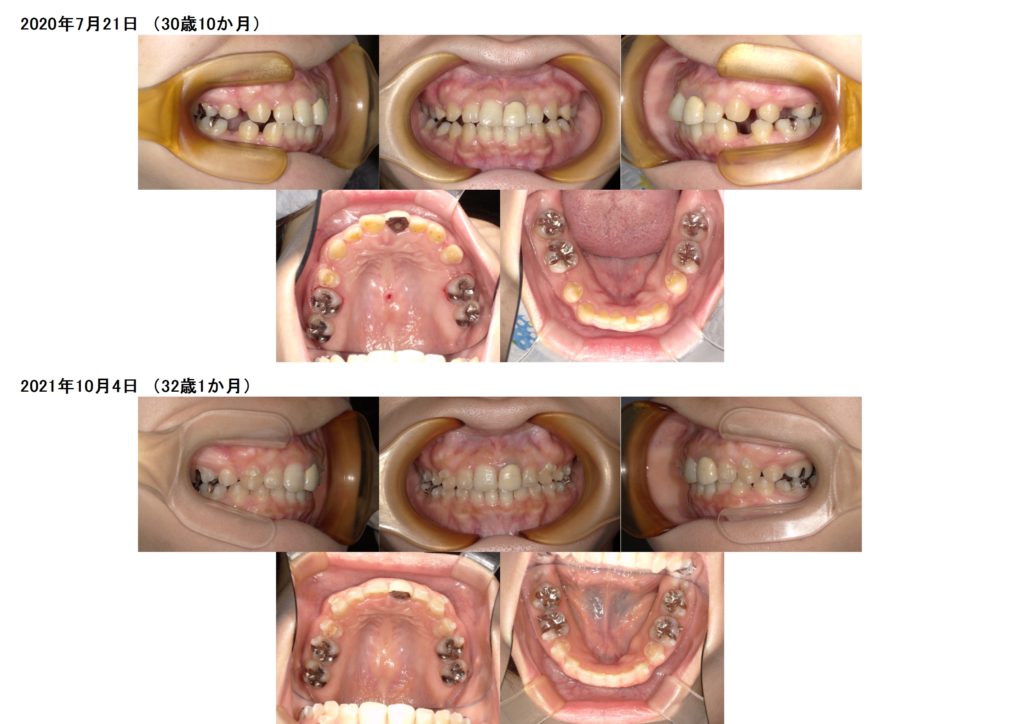

その後、マウスピースの治療に移ります。

抜歯した隙間も、前歯の位置も変化したのが分かると思います。

ここから微調整に入ります☺